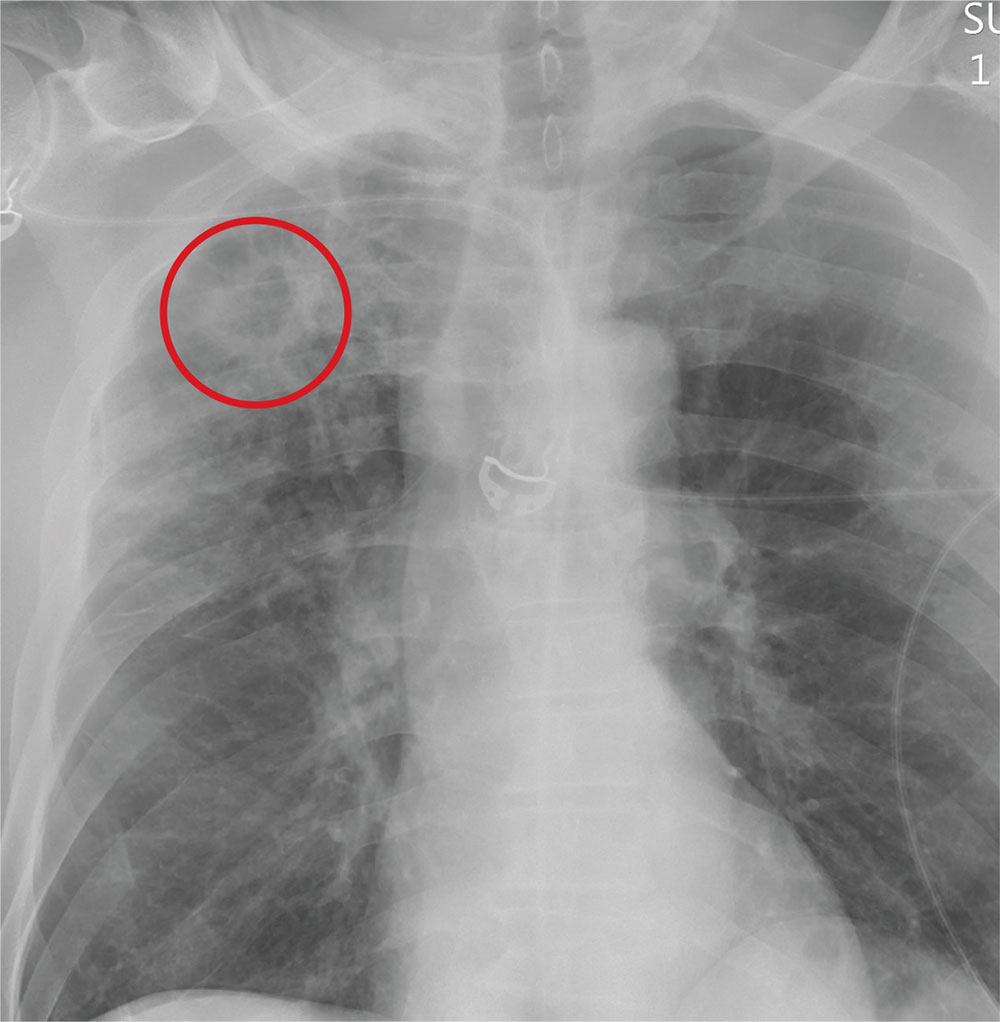

You order trauma lab tests and appropriate radiographic studies; a portable chest radiograph is completed (shown). What is your impression?

The radiograph demonstrates no acute fractures or pneumothorax. Of note is a right upper lobe infiltrate, which is a rounded cavitary lesion measuring approximately 4 cm. The differential includes pulmonary malignancy, active or previous pulmonary infection (eg, tuberculosis), or pneumatocele. Further evaluation with CT and a pulmonary consultation was coordinated.